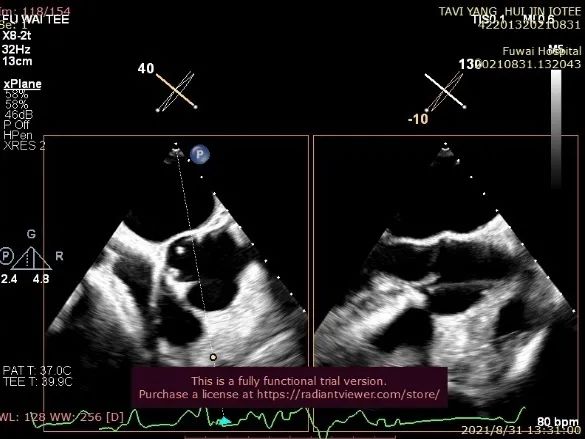

TA-TAVR在全麻和气管插管下进行。经右侧股静脉置入临时起搏器,经右侧股动脉在患者主动脉无冠窦内放置1根6F猪尾导管进行协助定位(图1)。

图1. TEE和放射线显示猪尾导管、临时起搏导线、导丝

透视下定位后第五肋间小切口进胸,打开心包,选择心尖裸区缝制六边形荷包。心尖穿刺后将泥鳅导丝过主动脉瓣经升主动脉、主动脉弓到达降主动脉膈肌水平,通过TEE确认细导丝没有与二尖瓣腱索缠绕(图2)。

图2. TEE和放射线显示输送器进入升主动脉根部、瓣环平面以上水平